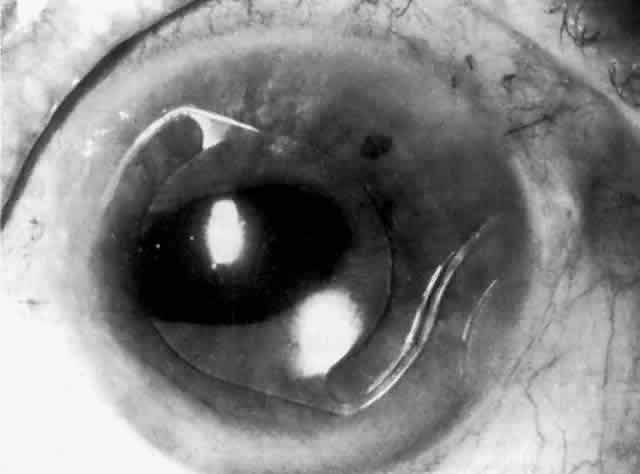

IOL-related inflammation is more commonly associated with some styles of lens implants than with others. Position of the lens or foreign material deposited on the lens during manufacture can also account for persistent inflammation. When the inflammation is associated with hyphema, it is termed UGH syndrome, which involves the triad of uveitis, glaucoma, and hyphema. UGH syndrome occurred more frequently in the 1970s, when iris-fixed lenses were commonly used.66,67 Today it is more often associated with anterior chamber lenses and is less likely to occur with posterior chamber lenses, although this has been reported.68,69 The mechanism is believed to be contact of the surface of the lens with the iris, causing mechanical irritation that may be enhanced by a poorly positioned or mobile lens implant. The loose posterior chamber lens may initially exhibit release of pigment due to friction on the posterior surface of the iris (pseudopigmentary glaucoma). This “windshield-wiper” effect alone can produce enough pigment to provoke an increase in IOP; however, it is the erosion into vascular tissue that results in hemorrhage, hyphema, and inflammation (Figs. 4 and 5).

Fig. 4. Posterior chamber lens implant with prolene haptics, with the patient's head in the primary position.

Fig. 5. Same posterior chamber lens implant as in Figure 4, but with the patient's head tilted, demonstrating mobility of the lens in the posterior chamber. (Courtesy of Dr. R. K. Parrish, Miami, FL.)

As mentioned in the Persistent Inflammation section, pseudopigmentary glaucoma is in many ways similar to the persistent inflammation that results from an IOL implant. The mechanism is believed to be contact of the surface of the lens with the iris. In persistent inflammation and UGH syndrome, typically either an anterior chamber lens or an iris-fixed lens is the culprit. With respect to pseudopigmentary glaucoma, however, the lens used is more likely to be a posterior chamber lens with the haptics (either one or both) positioned in the sulcus. In this way, the pigmented surface of the iris moves back and forth across the edge of the IOL, promoting release of pigment into the anterior chamber (see Figs. 4 and 5). The mechanism of IOP elevation is outflow obstruction from the excessive amounts of pigment granules and cell debris in the trabecular meshwork.